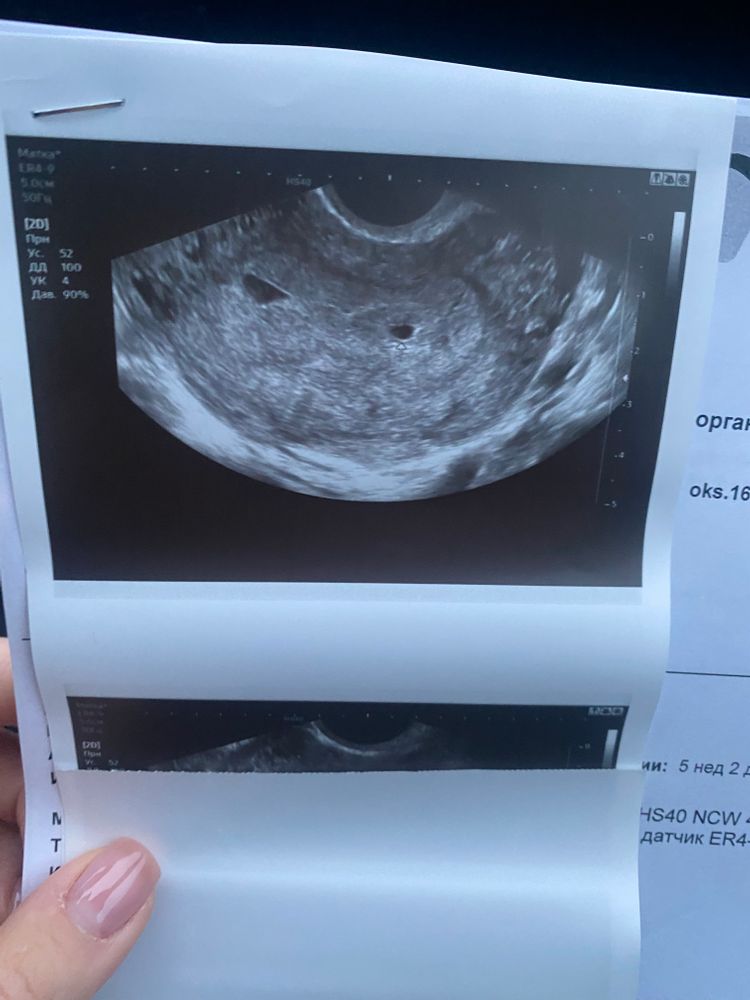

Деформация ПЯ

Срок 5 нед. 2 дня от месячных.

врач напугала, мне кажется, потому что пока все очень рано. Сказал, что ПЯ деформировано. Я не врач, не разбираюсь, но и не понимаю, в чем деформация. У кого была похожая ситуация?

У меня срок 5+4 по узи так же , врач сказал не переживать , это тут не главное. Была ещё на узи 5+1 по фото форма другая была , тоже деформирована , но выглядела иначе . В первом случае написали из за гипертонуса . Я тоже переживаю , но думаю все будет хорошо 👌 на 5+4 уже появился эмбрион . Ставлю утрожестан утром и вечером , и начали пить магнелис